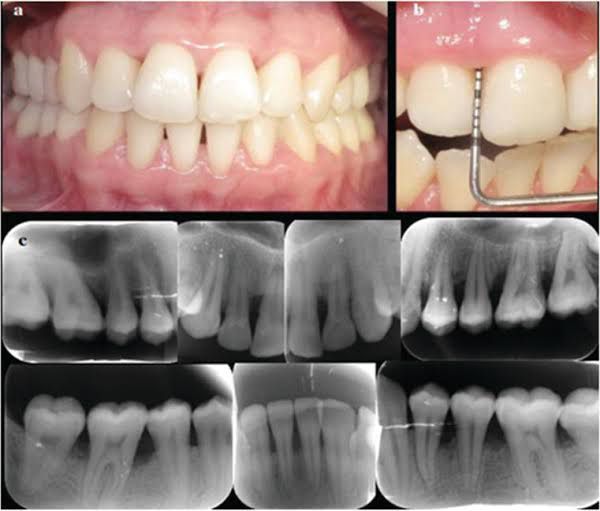

Aggressive periodontitis is a destructive disease characterized by the following: the involvement of multiple teeth with a distinctive pattern of periodontal tissue loss; a high rate of disease progression; an early age of onset; and the absence of systemic diseases.